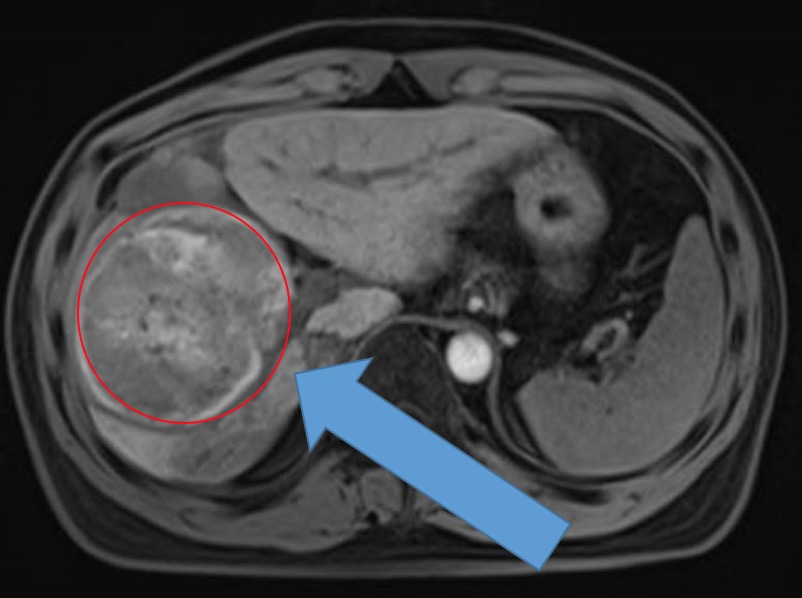

標記出肝右葉巨大腫瘤

去年9月,胡先生突然出現上腹劇烈疼痛,在當地醫院急診就醫,超聲檢查提示肝右葉巨大肝癌破裂出血,由於腫瘤體積巨大,當地醫院無法行手術治療,僅給予介入止血等保守治療,這個消息對胡某一家彷彿是一道晴天霹靂,平時身體一直康健的胡某怎麼也想不到自己會突然罹患這種不治之症。為了一絲生的希望,一家人輾轉廣、深多家醫院,然而各醫院均以腫瘤巨大,殘肝體積過小,手術風險過大等原因建議患者介入或靶向治療。

「他年輕,而且經過我們對殘肝體積的仔細評估,應該還有一線希望能為他保留『原裝』的肝臟。」車旭主任說,理論上如此,可實際上卻是難以上青天:一是腫瘤巨大,並且出現過破裂出血,大大增加了手術難度;二是經過早期11次的反覆治療,腫瘤與周圍組織血管炎性粘連明顯,給原本就十分困難的手術又帶來了極大的風險;三是位置很刁鑽,肝臟腫瘤緊緊的被多支血管包繞,像被一隻手緊握一樣,術中任何一支血管受損都會造成難以挽回的後果。